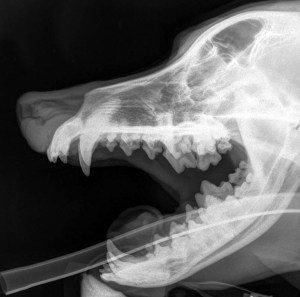

The website of the British Association of Homeopathic Veterinary Surgeons (BAHVS) features a case report in its ‘successful cases’ section, concerning a dog named Bedford (BAHVS, 2012). Bedford was diagnosed with a particularly nasty manifestation of a type of cancer, the squamous cell carcinoma, which appeared as a sizeable mass on top of his head, causing considerable pain and facial deformity.

From the photographs, it is clear the mass was initially large and painful, yet, after treatment, although the second photograph provided is from a slightly different angle, Bedford appears almost back to normal – the distortion of his brow and eyes seems to have gone and there is a keen look in his eyes.